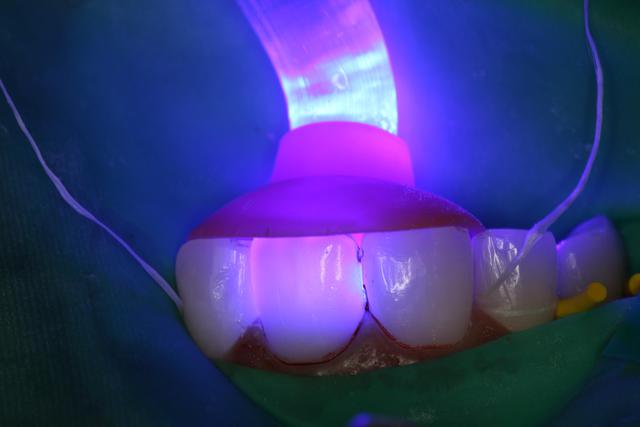

06/01/2012 à 01h31

J'ai posé un autre cas d'Emax avant hier pas trop mal, patient content.

Sur 21 très large sur laquelle j'ai fait apexification au MTA.

(Sur la photo, ce n'est pas un herpes, mais une chute en luge au ski...)

Variolink II teinte A3